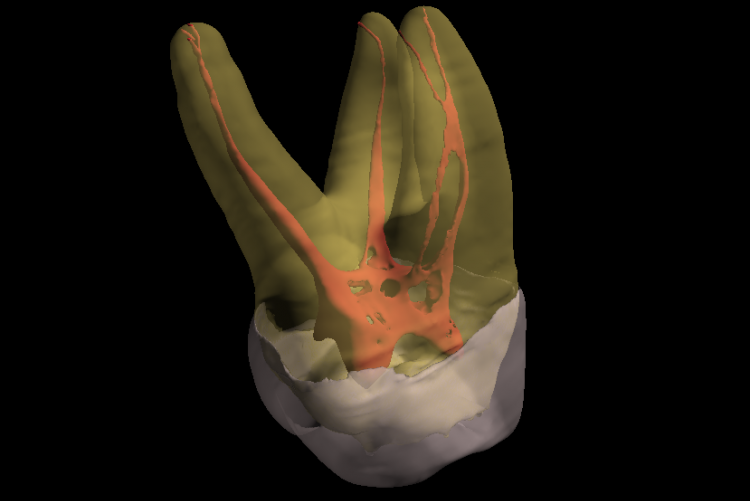

Conventional intra-oral radiography provides clinicians with cost-effective, high-resolution imaging that continues to be the front-line method for dental imaging. However, it is clear that there are many specific situations where the 3-D images produced by CBCT facilitates diagnosis and influences treatment. The usefulness of the CBCT cannot be disputed. It is a valuable task-specific imaging modality, producing minimal radiation exposure to the patient and providing maximal information to the clinician.